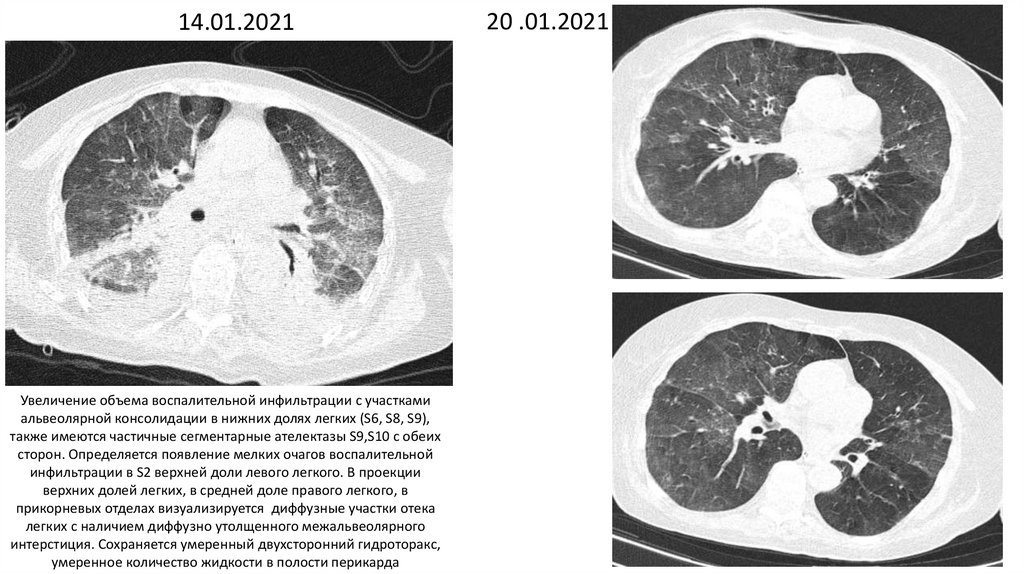

14.01.2021

Увеличение объема воспалительной инфильтрации с участками

альвеолярной консолидации в нижних долях легких (S6, S8, S9),

также имеются частичные сегментарные ателектазы S9,S10 с обеих

сторон. Определяется появление мелких очагов воспалительной

инфильтрации в S2 верхней доли левого легкого. В проекции

верхних долей легких, в средней доле правого легкого, в

прикорневых отделах визуализируется диффузные участки отека

легких с наличием диффузно утолщенного межальвеолярного

интерстиция. Сохраняется умеренный двухсторонний гидроторакс,

умеренное количество жидкости в полости перикарда

20 .01.2021